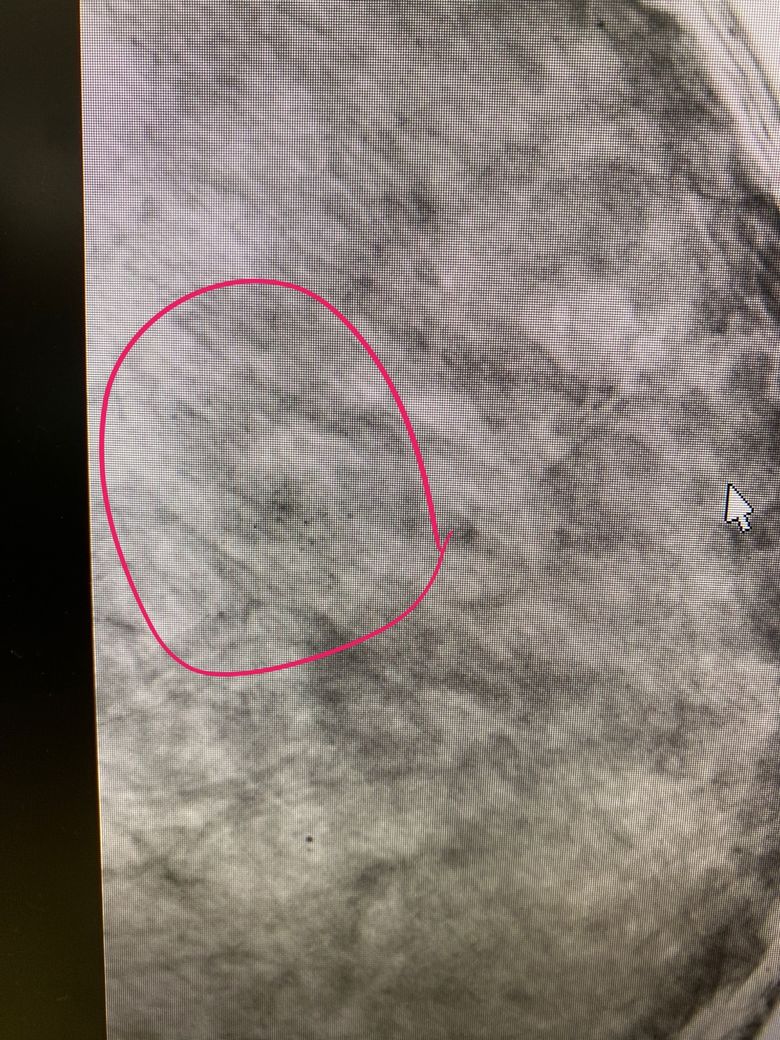

군집석회화인가요???

유방촬영술에서 미세석회가 발견되었고 유방확대술을 앞두고 있어 고민스러우시군요. 해당 병변은 군집석회화가 맞습니다만, 모든 군집석회화가 악성 종양을 시사하는 것은 아닙니다. 당장 관찰되는 병변은 양성에 가까워보이니 6개월 후 추적관찰을 권고하신 것이라 예상되고, 유방확대술을 시행하면 해당 병변의 추적 평가가 어려워지는 것은 사실입니다. 그러니 걱정스러우시면 이번에 발견된 석회병변의 6개월 뒤 변화를 확인하시고, 양성일 가능성이 더 높아지면 그 때 수술을 시행하는 것도 방법이 될 수 있겠습니다. 혹은, 집도하는 의사와 이 부분을 상의해보시고 진행하시기 바랍니다.

• microcalcification 의 가능성이 있어보입니다만 이는 영상의학과 전문의의 정확한 판독소견이 있어야 할 것으로 사료됩니다.

• 네 맞습니다. 군집석회화입니다

수술을 받으시는 것은 이에 대한 검사가 완전히 끝난 다음에 받으시는 편이 좋겠습니다

유방외과 진료를 받으보시기 바랍니다.